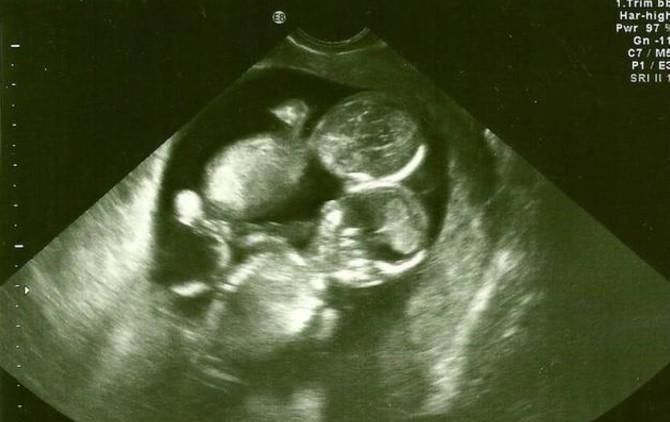

?所以夫妻俩就开始了他们的二胎计划,不到两个月琳琳终于怀上了,虽然家里经济条件并不是很好,既然已经怀上了,琳琳想着,就让他顺其自然吧,怀孕刚到三个月,这肚子就看着很大,琳琳心想不会又是双胞胎吧?

第二天,琳琳在老公的陪同下,来到医院做产检,过了一阵子医生说:“恭喜你们,怀的又是一对双胞胎。”此时的琳琳与老公非常的惊讶!老公小声的说了一句:“要是这回能生个儿子就好了。”医生听见后忍不住的笑了。